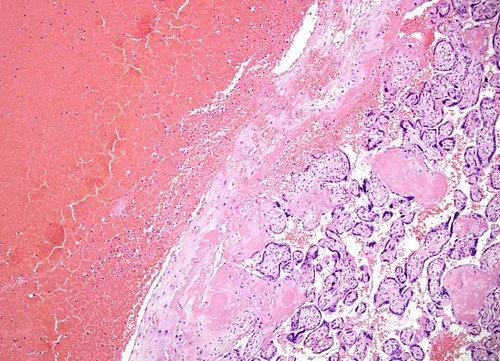

The four most common patterns of abnormal placentation/placental injury are:

Other subtypes include massive perivillous fibrin deposition, placental infarcts, and chorioangiosis.

Examples of abnormal immune placentation